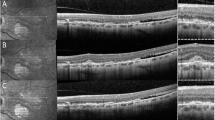

First described in 1961 [31], FA continues to be considered the reference standard for the diagnosis of mCNV [4]. In the studies included in this review, active mCNV was diagnosed on FA by well-defined hyperfluorescence in the early phase that increased in leakage size and intensity in the late phase [24,25,26, 28]. Associated blood or pigmentation showed as blocked fluorescence [26]. FA findings in inactive mCNV comprised hyperfluorescent staining of a macular scar due to fibrosis in the absence of leakage [9, 28]. Meanwhile on OCTA images, mCNV appeared as an abnormal network of bright interlacing or tangled vessels in the outer retina and choriocapillaris slabs [26, 28]. Bagchi et al. [26] additionally reported the presence of a tight vascular net and the combination of a perilesional halo with visible core were features that indicate the presence of active mCNV [26]. On SD-OCT scans, mCNV was accepted to present as a dome-shaped area of homogenous hyperreflectivity either below or above the retinal pigment epithelium [24, 26]. Other features of a positive diagnosis of mCNV on SD-OCT included an overlying fuzzy area, absence of external limiting membrane visibility, disrupted photoreceptor ellipsoid zone, presence of subretinal hyper-reflective material, and subretinal and/or intraretinal fluid [26, 28].